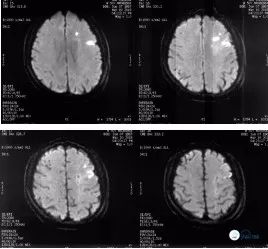

该患缘于入院前1月余无明显诱因出现发作性右侧肢体无力伴言语不清症状10余次,表现为言语笨拙,右上肢抬举无力、右手抓握能力下降,行走拖曳,向右侧倾斜,需人搀扶,每次持续约1-2分钟不等后,上述症状完全缓解。病程中患者无头晕、头痛,无恶心、呕吐,无视物模糊及视物旋转,无耳鸣及耳聋,无抽搐及意识不清。2018年5月6日就诊于北京某医院,完善头颅MRI:DWI示左侧基底节、放射冠、半卵圆中心、顶叶见点片状异常高信号(图1),诊断为“脑梗死”,住院静点药物(具体不详),治疗后患者未遗留症状;住院期间行头颈CTA提示:左侧颈内动脉闭塞(图2)故来诊。

头颅MRI(2018-05-10): DWI示左侧基底节、放射冠、半卵圆中心、顶叶见点片状异常高信号。(图1)